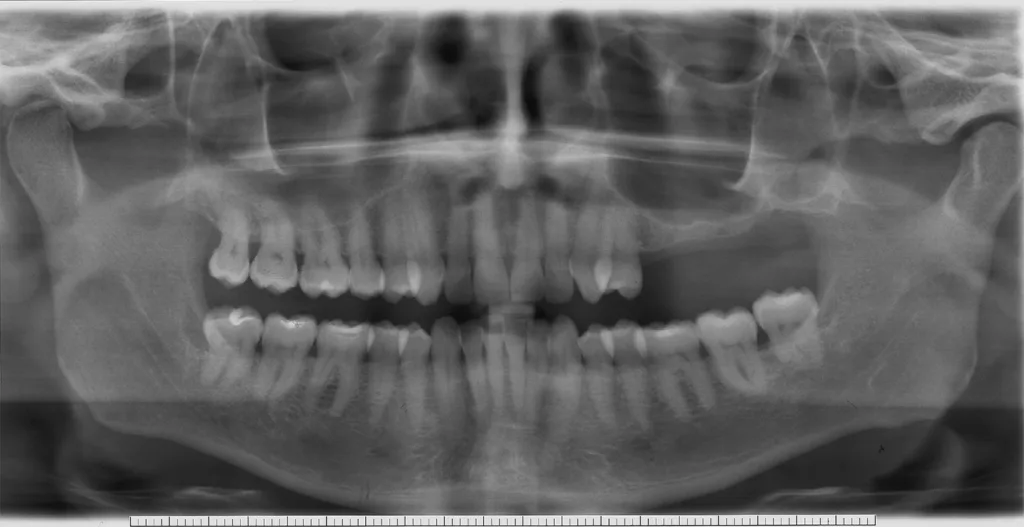

- Anatomie: Behandelte fortgeschrittene Parodontalerkrankungen sind klinisch stabil, zeigen aber in den implantatrelevanten anatomischen Knochenabschnitten (bukkale Lamellen, interapproximales Septum) weitere Abbauvorgänge durch Entzündung (Abb. 1 und 2) [1].

Daraus resultiert ein zweizeitiges Vorgehen mit (i) Entfernung prognostisch unsicherer Zähne, (ii) parodontaler Zieltherapie zur Sicherung des Restzahnbestandes, ergänzt durch (iii) mikrochirurgische Revision tiefer Resttaschen vor Implantation zum weiteren Entzündungsschutz (Abb. 3 und 4). Die Implantatplanung bleibt vorläufig. Ein definitiver Kostenvoranschlag wird erst nach funktioneller Entlastung und digitaler Beurteilung der Implantatknochenanatomie erstellt.

- Anatomische Information: Mehrinformationen sind die Nähe zum N. alveolaris, die Ausdehnung der Kieferhöhle und ihrer Septen, der Verlauf (insbesondere transversal) und die Mineralisation des Implantatknochens (nach Zahnextraktion) sowie die Positionierung des/r Implantate/s in Relation zu Nachbarzähnen (Abb. 9 und 10). Durch Schrägmessungen resultieren auch im DVT-Messfehler von bis zu 1 mm [5,6].